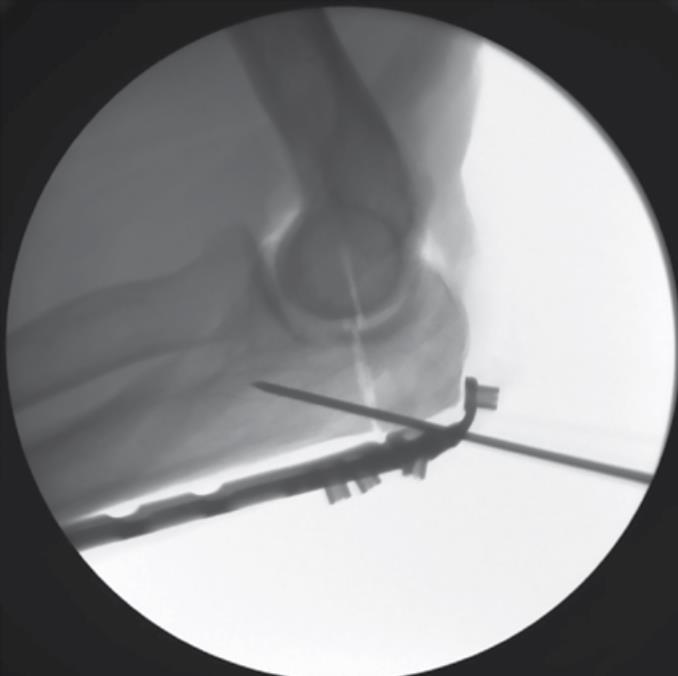

• Cannulated 3.0 PLS Setup (optional)

• if a Polyaxial Locking Screw is needed in any of the threaded holes, use the T-10 driver to remove the PDG if present and insert the 1.1mm PLS AIMing Guide

• insert a 1.1mm K-Wire through the PLS AIMing Guide in the desired trajectory until the far cortex is reached

• note: fluoroscopy is helpful to confirm the trajectory of the K-Wire

• Fluoroscopic Confirmation

• after confirming the K-Wire reaches the far cortex, use the cannulated 3.0 PLS T-10 Driver to remove the PLS AIMing Guide, leaving the K-Wire in place

• Cannulated 3.0 PLS Preparation

• slide the cannulated Depth Gauge over the K-Wire to measure the appropriate length of screw

• using the 2.4mm cannulated PLS drill bit, drill over the K-Wire to the proper depth

• Cannulated 3.0 PLS Fixation

• using the Cannulated 3.0 PLS T-10 driver, thread the screw down the K-Wire until the head of the screw contacts the plate

• remove the K-Wire and fully lock the screw to the plate using the non- cannulated T-10 Driver.

• using fluoroscopic imaging, confirm that proper reduction has been maintained and that all screws are of proper length and fully engaged to the plate

• confirm that all PDGs have been removed.